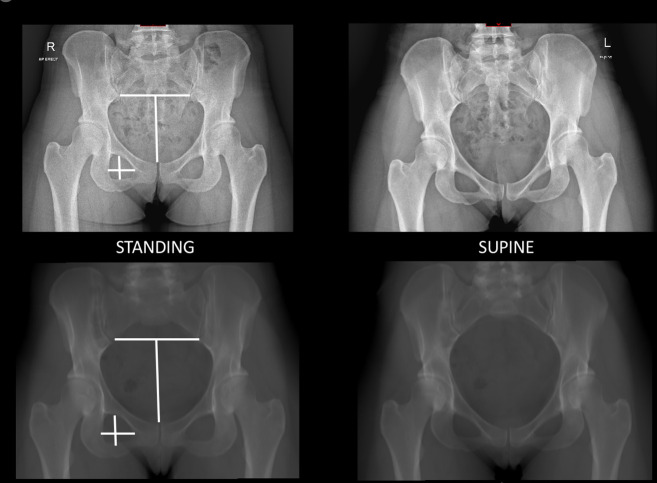

Methods: In total, 60 patients were selected from an institutional database: 20 with acetabular retroversion (AR), 20 with developmental dysplasia of the hip (DDH), and 20 with cam-type femoroacetabular impingement (FAI). Multiplanar CT reformats were created and the sagittal rotation was aligned to the APP. The sagittal pelvic orientation was then corrected until the anteroposterior (AP) projection mirrored that of their preoperative supine and standing plain radiographs. The change in sagittal pelvic tilt angle required was measured.

Results: The mean deviation from the APP in the AR group was 11.55° (SD 4.96°) for supine radiographs and 3.28° (SD 8.66°) for standing radiographs. The mean deviation from the APP in the DDH group was 12.2° (SD 4.26°) for supine radiographs and 6.96° (SD 3.43°) for standing radiographs. The main deviation from the APP in the FAI group was 8.63° (SD 5.21°) for supine radiographs and -1.28° (SD 7.31°) for standing.